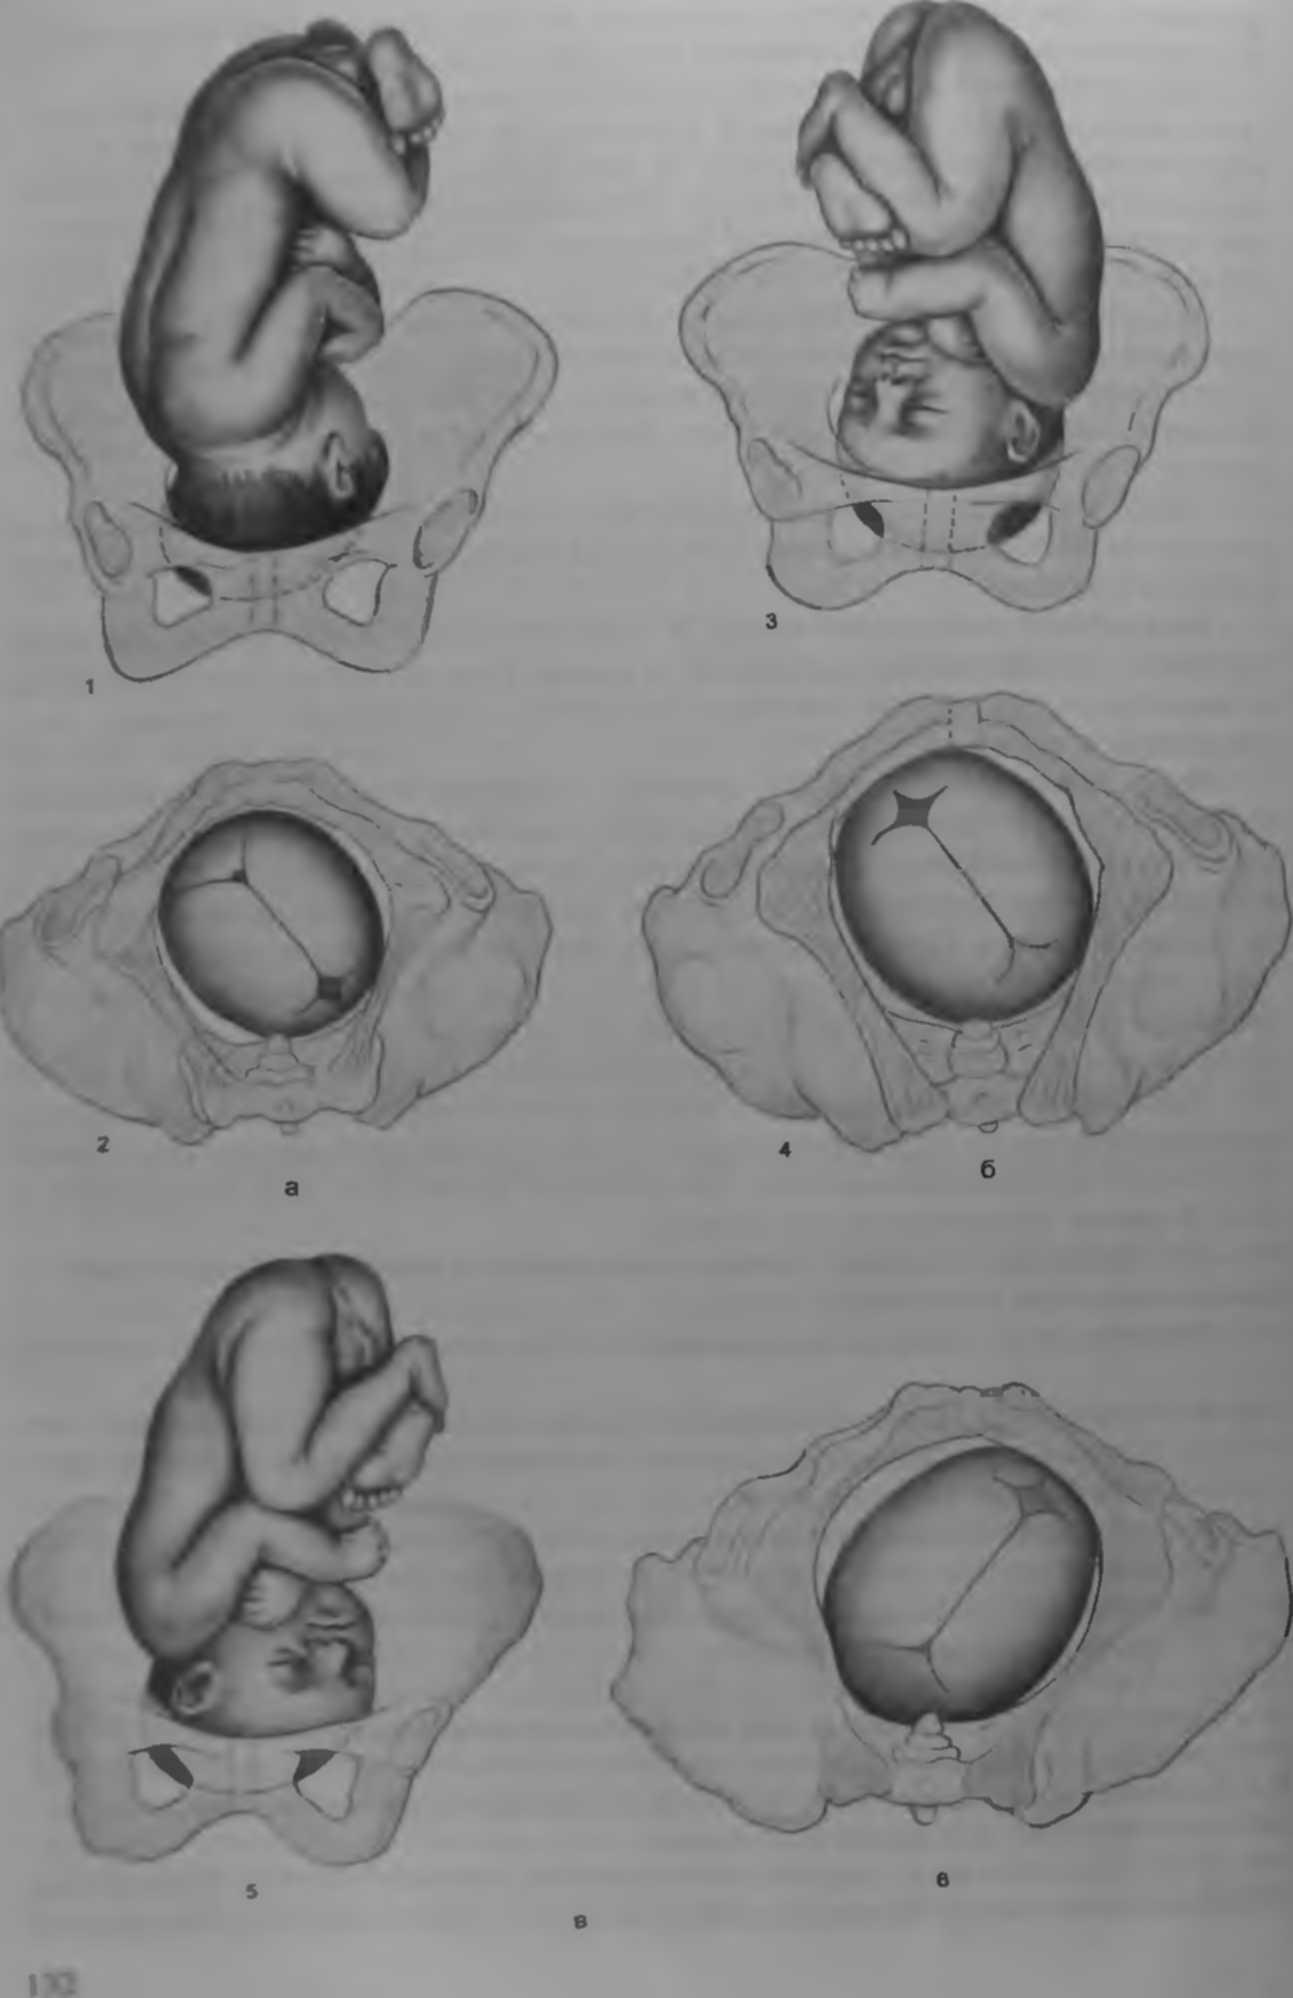

Во время беременности, положение плода имеет большое значение для мамы и малыша. Одним из типичных положений является продольное предлежание головное. В этом положении голова малыша находится внизу, а ножки - наверху. Это положение достаточно распространено и предпочтительно для естественных родов.

Фото положения плода во время беременности

Ниже приведены несколько фотографий, которые помогут вам визуализировать положение плода во время беременности.